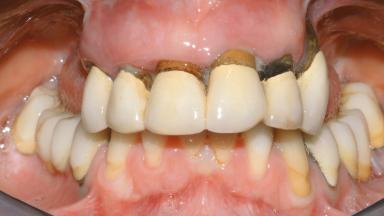

Conventional Loading of Eight Implants in the Maxilla and Final Restoration with a Full-Arch Gold-Ceramic FDP

A 35-year-old Caucasian female presenting with advanced periodontal disease involving both the maxillary and the mandibular dentition was referred for evaluation. The patient, a non-smoker in good general health, requested treatment for recurrent periodontal abscesses, tooth mobility, and discomfort during chewing, as well as restoration of her missing teeth with a fixed prosthesis to improve mastication and esthetics. All residual maxillary teeth exhibited plaque deposits, deep pockets, bleeding on probing, and class III mobility and were evaluated as hopeless. All residual mandibular teeth except tooth 37 could be maintained after periodontal therapy.